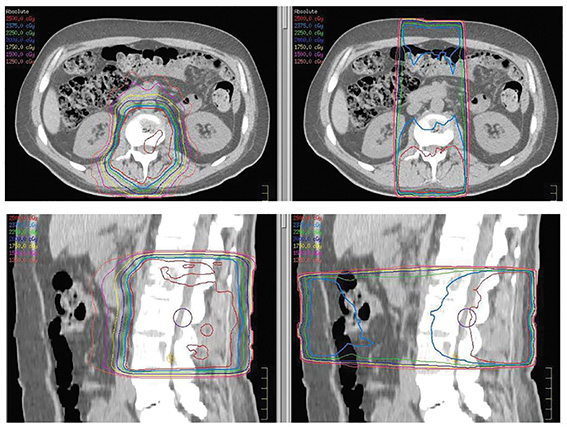

Genesis CancerCare centres in Bunbury, Joondalup, Murdoch and Wembley offer VMAT—volumetric-modulated arc therapy—a technique which reduces any potential side-effects patients may experience.